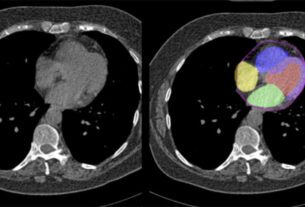

![]() | Future of medical imaging innovation is hereInnovation in radiology and imaging has been an area of increased focus in the medical industry over the past decade, with new technologies and visualisation advancements emerging at a rapid pace. Artificial Intelligence (AI)… — Omnia Health Insights |